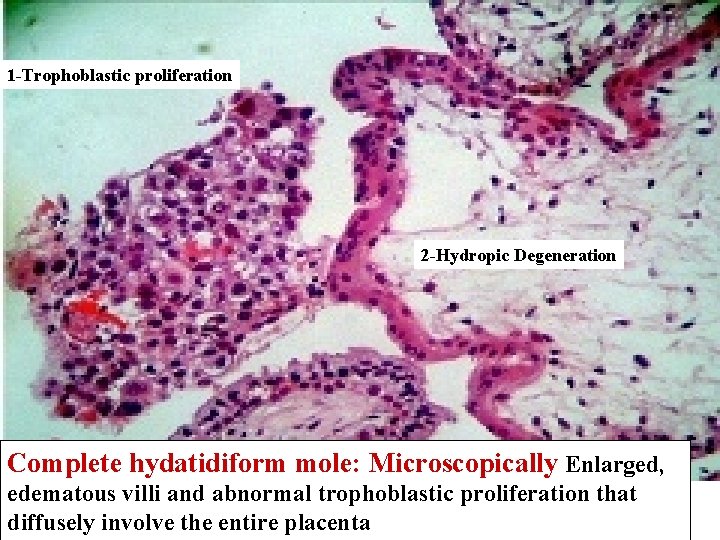

1 -Trophoblastic proliferation 2 -Hydropic Degeneration Complete hydatidiform mole: Microscopically Enlarged, edematous villi and abnormal trophoblastic proliferation that diffusely involve the entire placenta